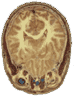

What if... machines

could predict a future neurological or mental disease?Brain imaging can identify structural and functional differences in people with various neurological and mental disorders. For example, magnetic resonance imaging has shown that people with schizophrenia have larger than normal lateral ventricles, reduced hippocampus size, changes in the size of basal ganglia nuclei, and abnormalities in the prefrontal cortex. Currently, genetic testing can be used to screen for particular illnesses, such as Huntington's disease. Perhaps a brain scan will enable detection of other neurological and mental disorders.